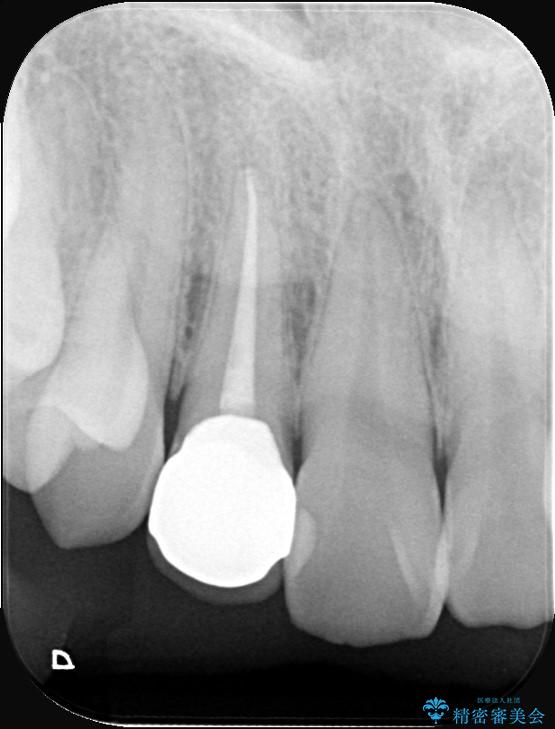

右上2番の歯に自発痛を認め、症状や歯髄診・レントゲン像から不可逆性歯髄炎と診断し、精密根管治療から歯冠補綴まで行うこととなりました。

初診時に歯髄診断を行い、不可逆性歯髄炎と診断し抜髄から補綴修復までの流れを説明し、精密根管治療、ファイバ-コア築造、オールセラミッククラウン(St)修復を行うこととしました。